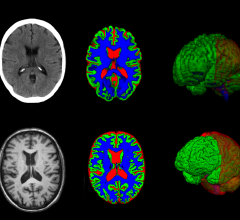

July 16, 2025 — A scientific team supported in part by the National Institutes of Health (NIH) has developed a new ...